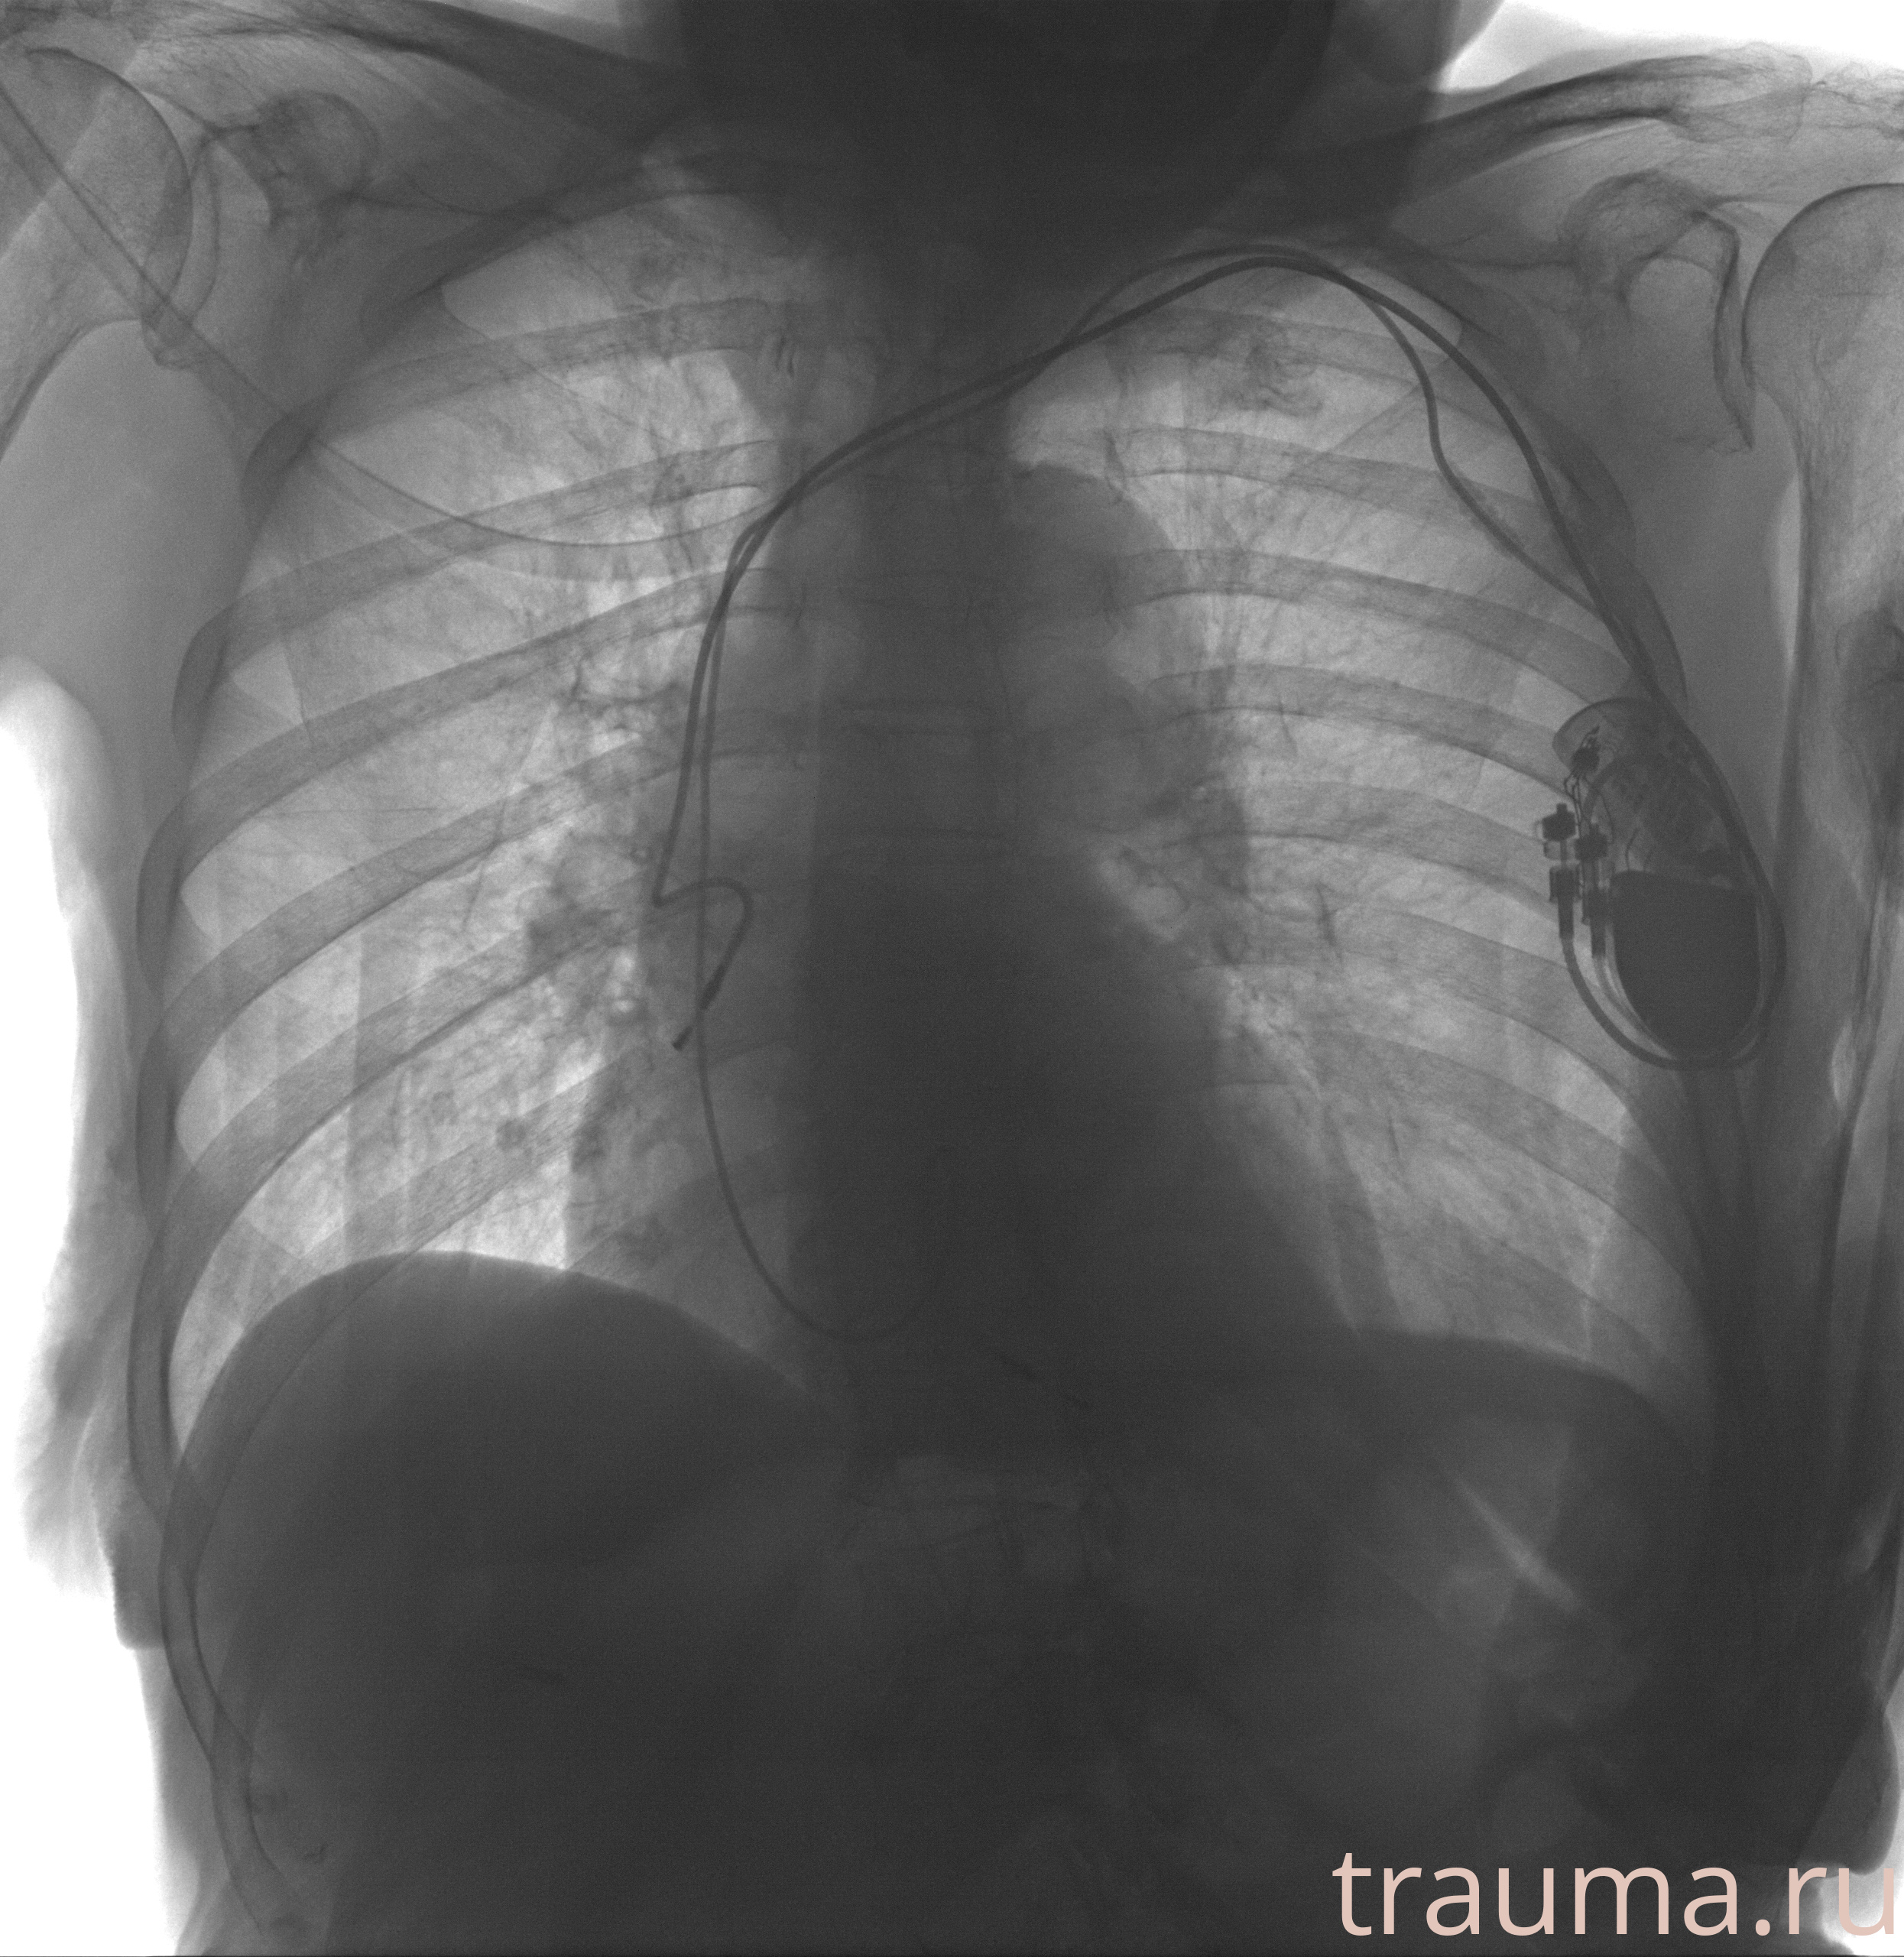

Рентгенограммы

Рентген на дому: по вашему адресу приезжает врач-рентгенолог, травматолог-ортопед с мобильным рентгеновским аппаратом, проводит диагностику травмы или заболевания, делает необходимые рентгенограммы, дает рекомендации по дальнейшему лечению. Получить качественные снимки в домашних условиях возможно благодаря уникальной методике, разработанной МосРентген Центром для института  Склифосовского

при переломе шейки бедра и пневмонии от компании МосРентген Центр - партнера Института имени Склифосовского